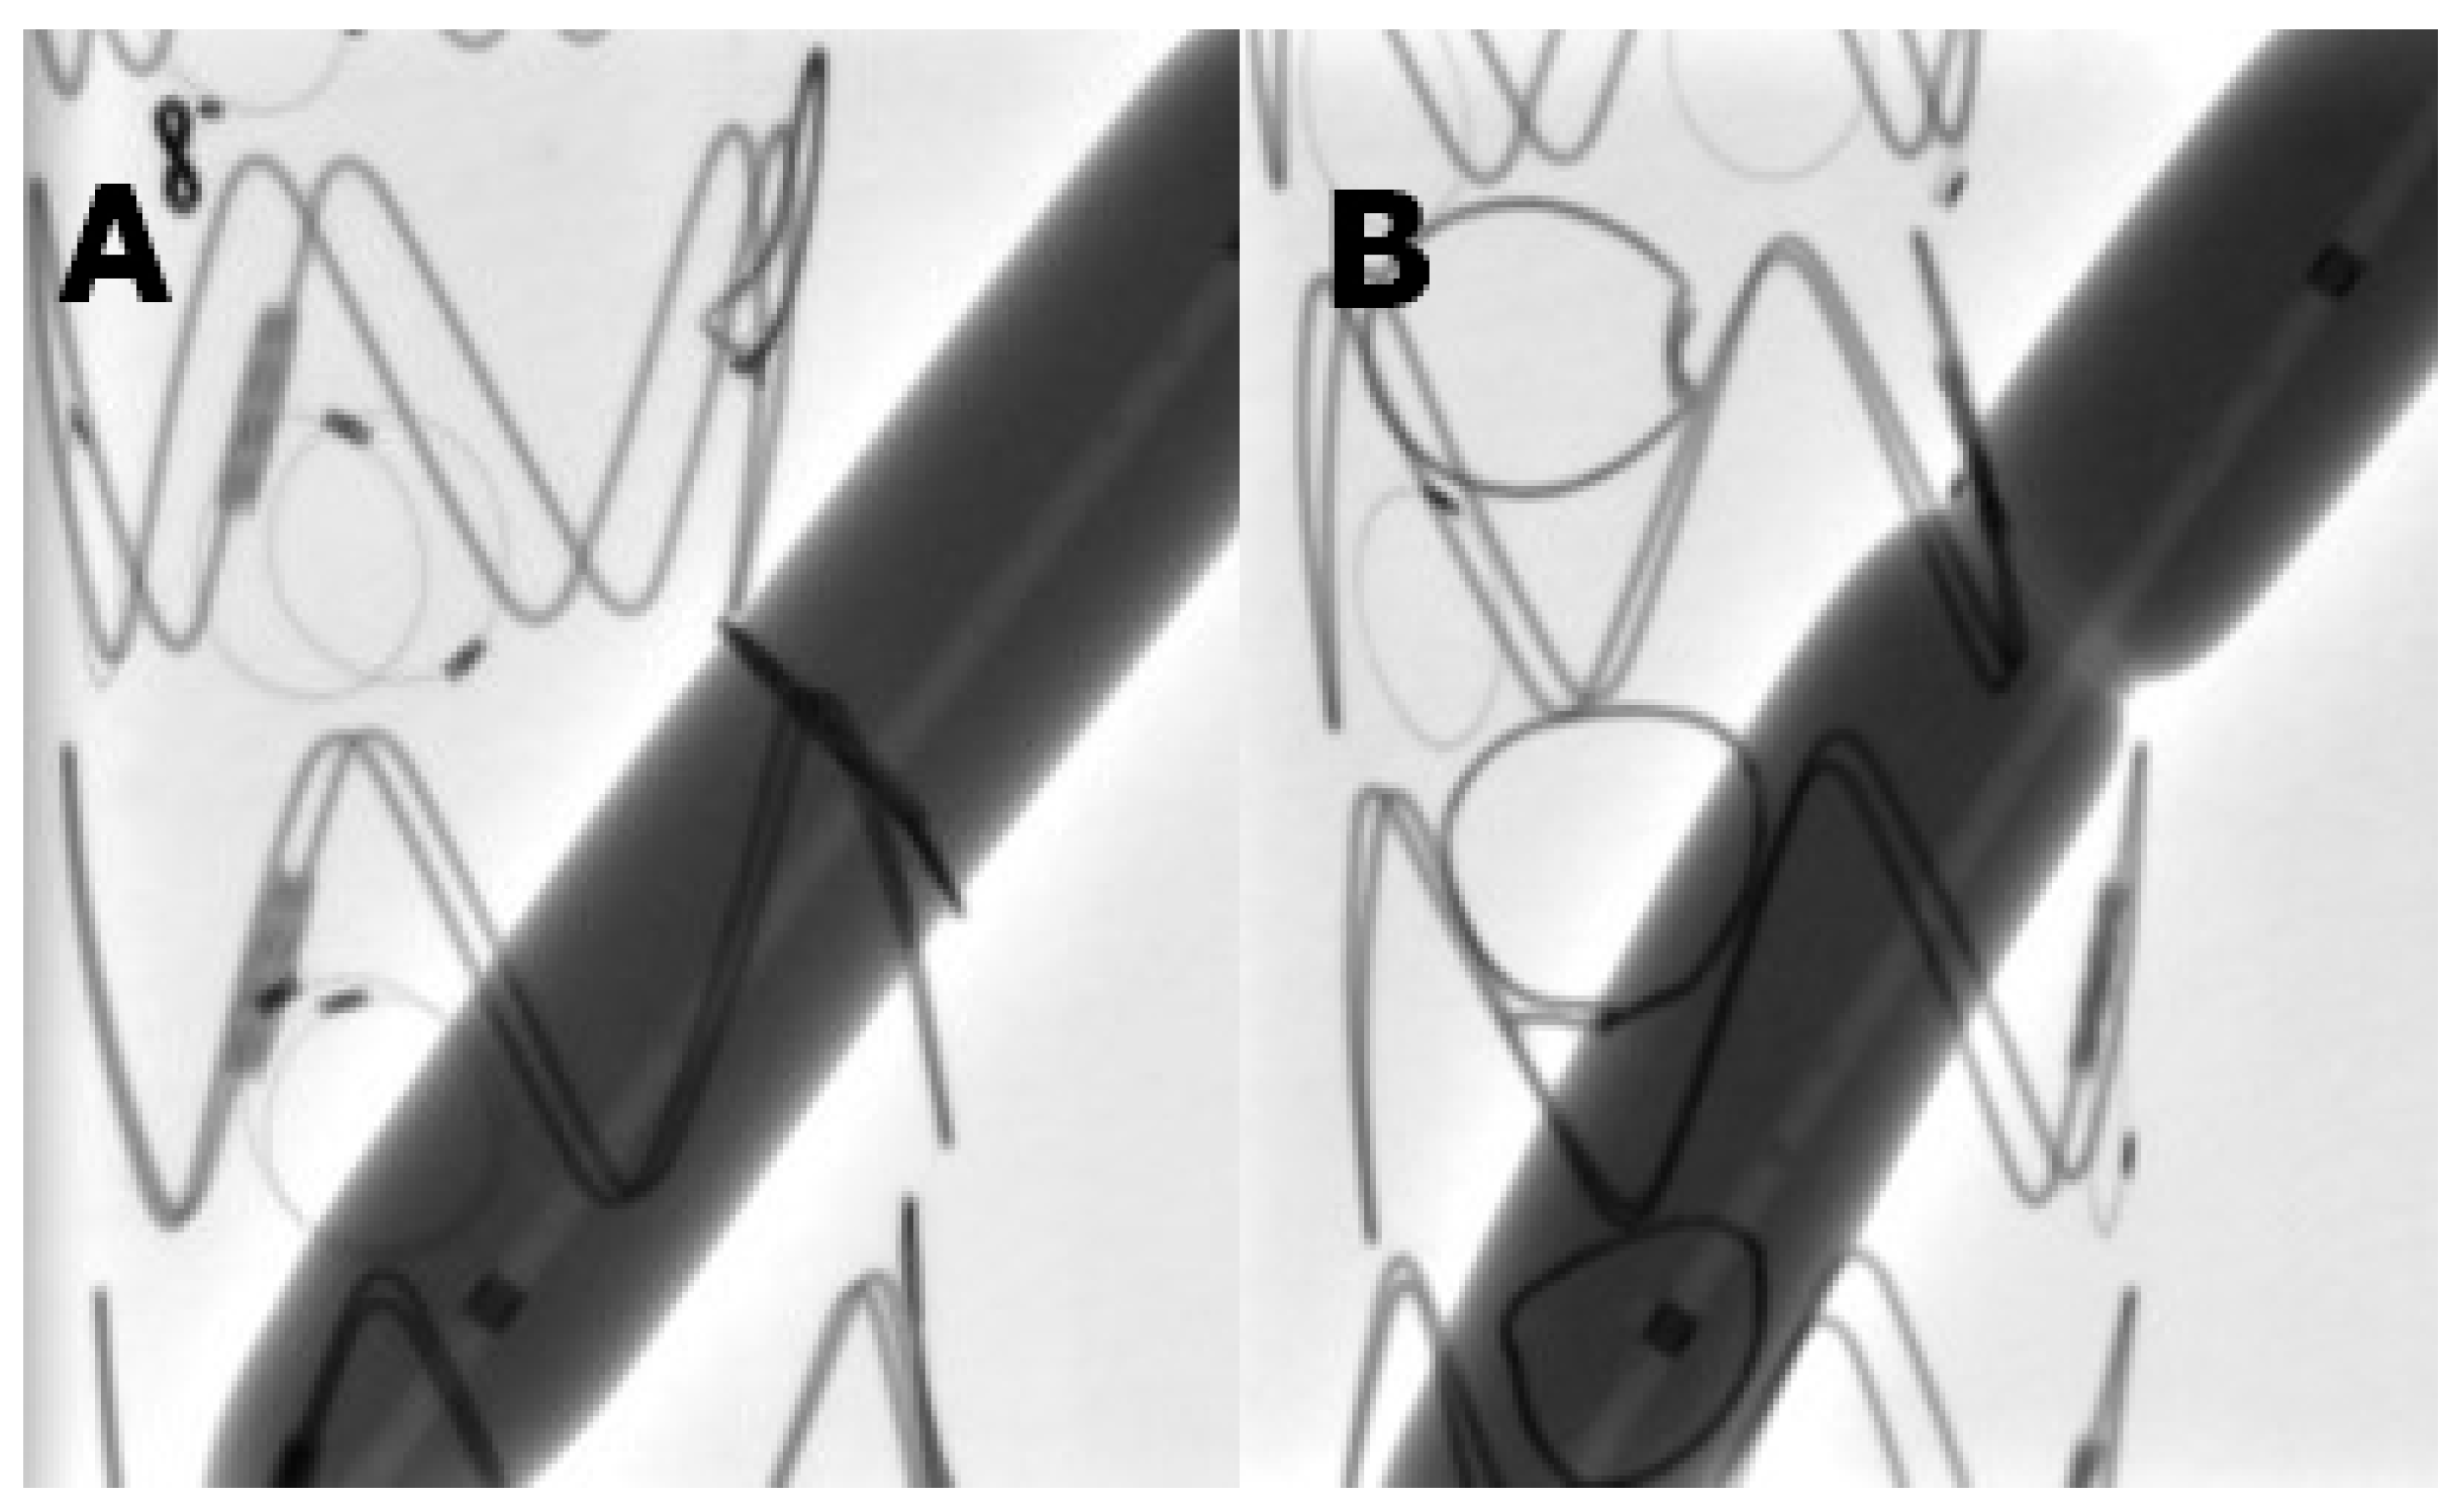

During balloon dilatation tests, all fenestrations reinforced with a snare loop demonstrated an effacement of the indentation already at pressures below the nominal pressure at 6 atm (Figure 1A). On the contrary, the Hungaroring resisted over-expansion even at 21 atm, which is way above RBP in every case (Figure 1B). High-resolution and high-magnification macro images show that Hungaroring resisted the expansion without any significant and visible distortion (Figure 2).

Figure 1.

(A) No indentation even below 8 atm (B) Hungaroring resisted over-expansion even at 21 atm.